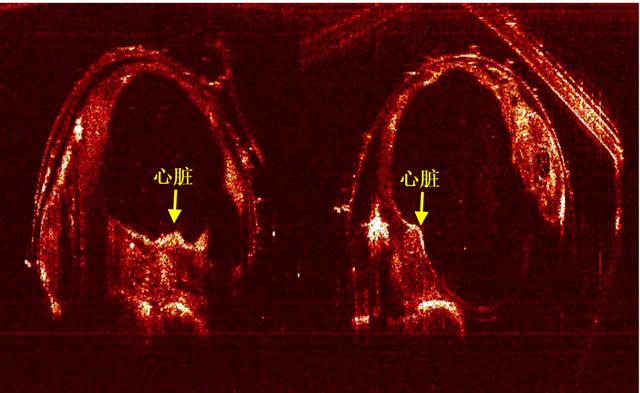

该作品在决赛演示中,被用于对直径1mm的鱼胚胎进行活体成像,实时展现了鱼胚胎的心脏跳动和血液流动,得到了评审专家和现场观众的一致认可。

本作品所获得的直径1mm鱼胚胎在两个正交方向上的断层图像